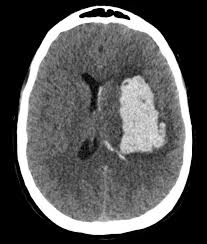

ميزة أخرى وفائدة. الأدوية الخافضة للكوليسترول مرتبطة بانخفاض خطر حدوث نزيف السكتة الدماغية ▫️ الأشخاص الذين يتناولون عقاقير خفض الكوليسترول المسماة الستاتينات قد يكونون أقل عرضة للإصابة بنوع من السكتة الدماغية يسمى النزف داخل المخ ، وفقًا لدراسة جديدة نُشرت في The Neurology® ،

نُشرت في The Neurology® ، المجلة الطبية للأكاديمية الأمريكية لطب الأعصاب. ▫️ بالنسبة للدراسة ، ألقى الباحثون نظرة على السجلات الصحية في الدنمارك وحددوا 989 شخصًا بمتوسط ​​عمر 76 عامًا يعانون من نزيف داخل المخ في منطقة الفص في الدماغ. وتم مقارنتهم بـ 39500 شخص .

لم يصابوا بهذا النوع من السكتات الدماغية وكانوا متشابهين في العمر والجنس وعوامل أخرى. وجد الباحثون أن الأشخاص الذين يستخدمون الستاتين في الوقت الحالي لديهم خطر أقل بنسبة 17٪ للإصابة بسكتة دماغية في مناطق الفص في الدماغ وخطر أقل بنسبة 16٪ للإصابة بالسكتة الدماغية .

16٪ للإصابة بالسكتة الدماغية في المناطق غير الفصية بالدماغ. ▫️ عند استخدام العقاقير المخفضة للكوليسترول لأكثر من خمس سنوات ، كان لدى الأشخاص خطر أقل بنسبة 33٪ للإصابة بسكتة دماغية في منطقة الفص و 38٪ أقل من خطر الإصابة بالسكتة الدماغية في المنطقة غير الفصية من الدماغ.